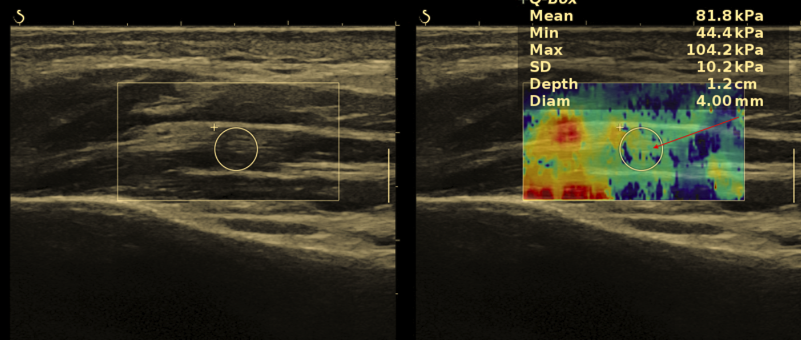

Badanie jest nieinwazyjne, dostępne i może być wielokrotnie powtarzane w trakcie leczenia. - Elastografia – jakościowa ocena napięcia mięśni

Szczególne znaczenie ma badanie elastograficzne, które umożliwia ocenę sztywności mięśni, a więc pośrednio stopnia ich napięcia. Dzięki temu można obiektywnie określić:

czy napięcie mięśniowe jest zwiększone,

jak bardzo odbiega od normy,

które mięśnie wymagają terapii.